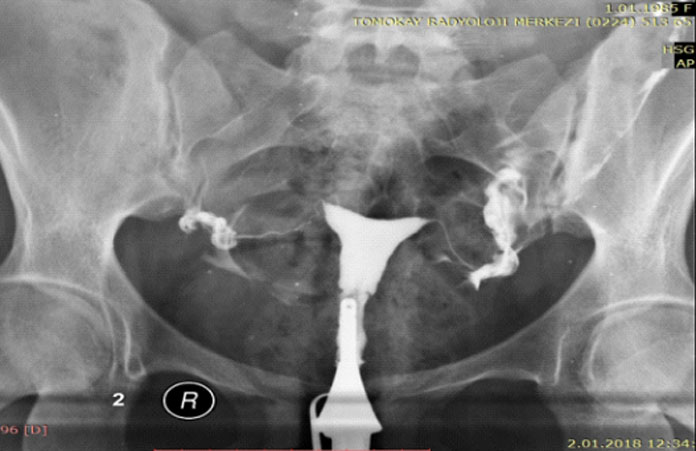

مع فيلم HSG ، يتم تشخيص وجود المرض في الرحم والأنابيب بشكل نهائي.

في الفيلم ،اذا وجد تشوهات خلقية في الرحم وتمدد طفيف للأنابيب. سيتم علاج الحالة بهذا التشخيص.

يحدد التصوير بالرنين المغناطيسي (HSG) بشكل قاطع ما إذا كان هناك مرض في الرحم وقناتي فالوب.